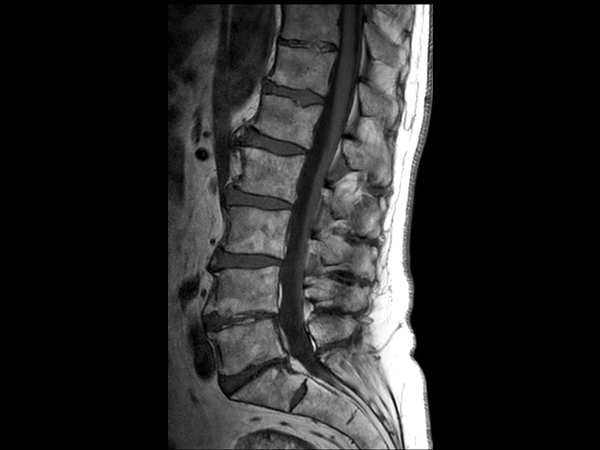

Comprehensive Lumbar Spine imaging at 3.0T